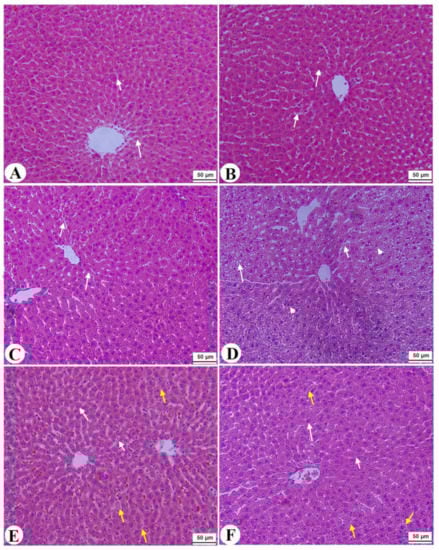

3.7. Histological Alterations